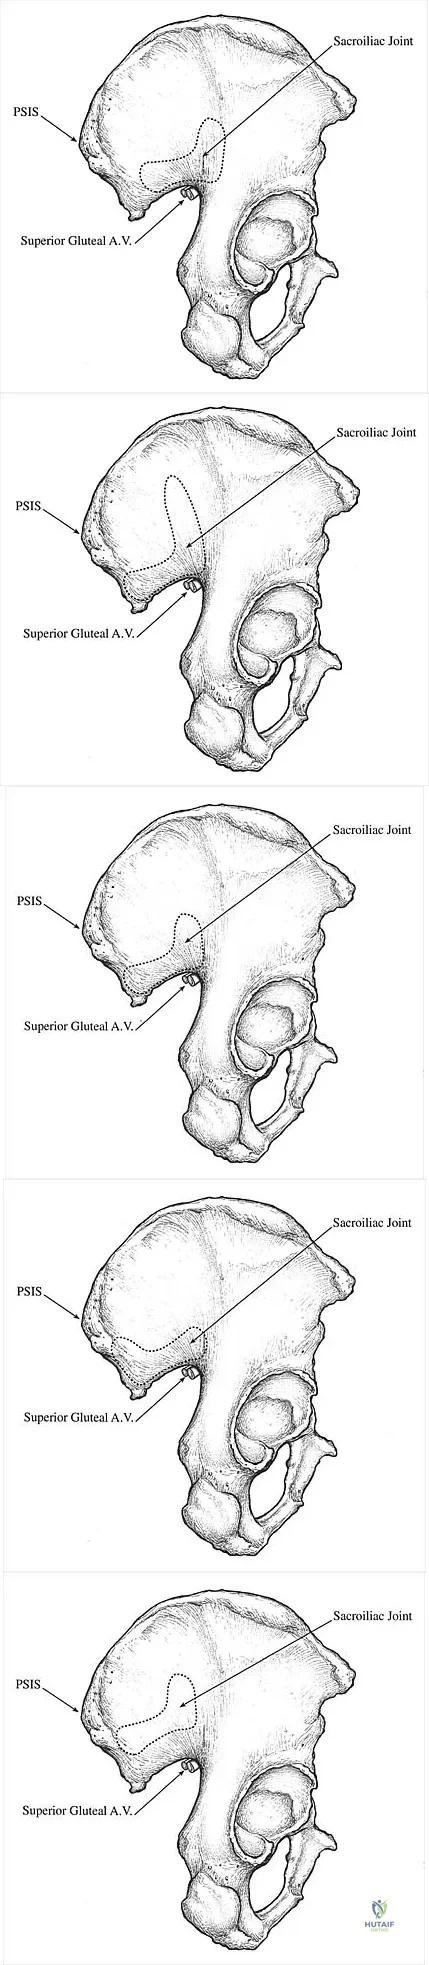

Question 46

Which of the following illustrations shown in Figures 21a through 21e correctly shows the projection of the sacroiliac joint on the outer table of the ilium?

Explanation